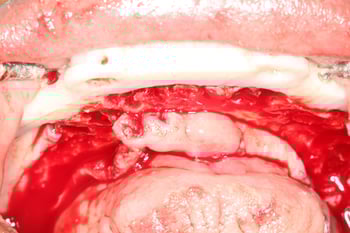

With the proposed tooth position defined, we predicted the ideal lower occlusal plane, which revealed the need for significant bone reduction.

Our primary objective was to achieve proper vertical dimension and sufficient restorative space to support a future implant overdenture, with a minimum clearance of 12–15 mm.

Computer-generated surgical guides were then used to facilitate precise bone reduction in both arches, reinforcing the value of prosthetic-driven planning.